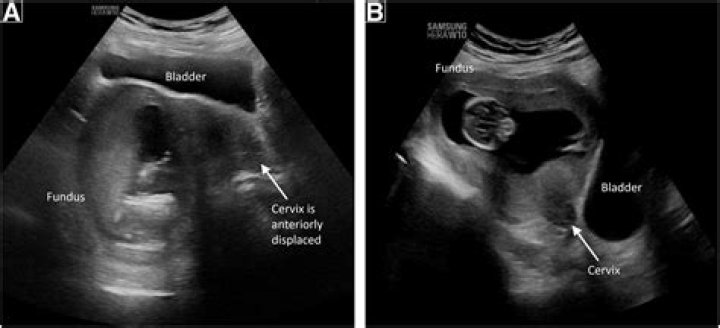

Having a tilted uterus (also called an inverted uterus, tilted cervix, or retroverted uterus) is perfectly normal. It just means that your uterus is tilted backward toward your spine rather than forward. A retroverted uterus has no effect on your ability to get pregnant.

Can you get pregnant with a retroverted uterus? Absolutely! The position of your uterus is not related to your fertility, and a retroverted uterus alone will not affect your ability to get pregnant.

Retroversion of the uterus is common. Approximately 1 in 5 women has this condition. The problem may also occur due to weakening of the pelvic ligaments at the time of menopause. Scar tissue or adhesions in the pelvis can also hold the uterus in a retroverted position.

The positioning of the uterus can change from anteversion to retroversion due to the filling of bladder or during pregnancy; however, changing from retroverted to anteverted position without prior pregnancy or endometriosis is rather uncommon.